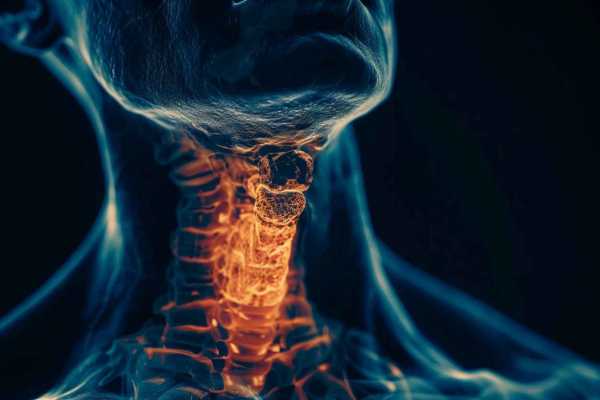

Узнайте о симптомах заболеваний щитовидной железы. Как распознать признаки гипотиреоза и гипертиреоза, важность своевременной диагностики и лечения.

Хорошее самочувствие и нормальное функционирование организма обеспечивается различными органами и системами. К числу самых важных из них относится щитовидная железа, отвечающая за выработку определенных гормонов. Данный орган влияет на состояние сердца и сосудов, обменные процессы в организме. Синтез гормонов трийодтиронина и тетрайодтиронина в недостаточном количестве приводит к образованию холестерина, из-за чего увеличивается риск развития инфарктов и инсультов.

Именно поэтому симптомы заболевания щитовидной железы заслуживают самого пристального внимания, их важно вовремя диагностировать и принять надлежащие меры для улучшения состояния здоровья. В этой статье Клео.ру предлагает разобрать основные моменты, связанные с заболеваниями данного органа.